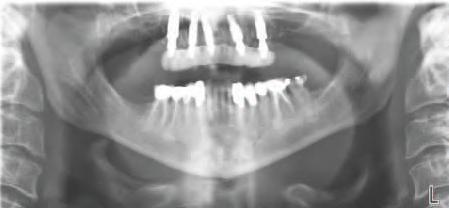

PREZENTARE CLINICĂ

O pac entă de 61 an s-a prezentat la Per odont cs/Per odontal Prosthes s Cl n c d n cadrul Un vers ty of Pennsylvan a School of Dental Med cne dor nd în pr nc pal să a bă „d nț f xaț ” în locul protezelor mob le ex stente (f g. 1). După f nal zarea unu examen stomatolog c cupr nzător, nclus v exam narea extra- ș ntraorală, evaluarea pr n tomograf e computer zată cu fasc cul con c (CBCT), fotograf erea dentară ș întocm rea f șelor dentare, s-a creat un plan pentru real zarea une reab l tăr full-mouth folos nd mplantur ș proteze dentare f xe. Pac enta purta proteze totale moble retenț onate pe m n - mplantur atât la mand bulă, cât ș la max lar. În t mpul evaluăr n ț ale, ea ș -a expr mat preocupăr le legate de estet ca restaurăr lor ex stente în ceea ce pr vește expunerea g ng vală ș

forma/măr mea d nț lor (f g. 2,3). Ca parte a colectăr de date necesare pentru faza d agnost culu ș plan f căr d g tale, supraprotezele ex stente urmau a f ut l zate pentru a crea modele dentare, reprezentând partea nternă a acestor restaurăr . O înreg strare cu arc fac al ș o înreg strare a ocluz e urmau a f ut l zate pentru a remonta cl n c aceste modele folos nd restaurăr le ex stente.

Figurile:

1. Imaginea intraorală a protezelor existente retenționate de miniimplanturi la prezentarea inițială.

2. Pacienta prezenta expunerea excesivă a componentei gingivale din protezele existente.

3. Situația pretratament mandibulară edentată cu cele patru mini-implanturi existente.